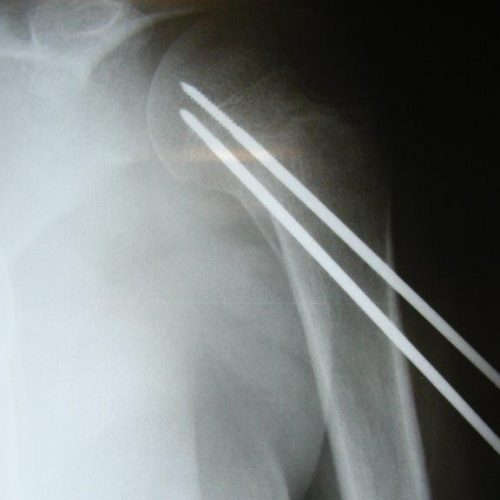

ΚΑΤΑΓΜΑ ΒΡΑΧΙΟΝΙΟΥ-ΚΑΤΑΓΜΑ ΥΠΟΚΕΦΑΛΙΚΟ-ΠΑΙΔΙΚΟ

ΚΑΤΑΓΜΑ ΥΠΟΚΕΦΑΛΙΚΟ ΠΑΙΔΙΚΟ